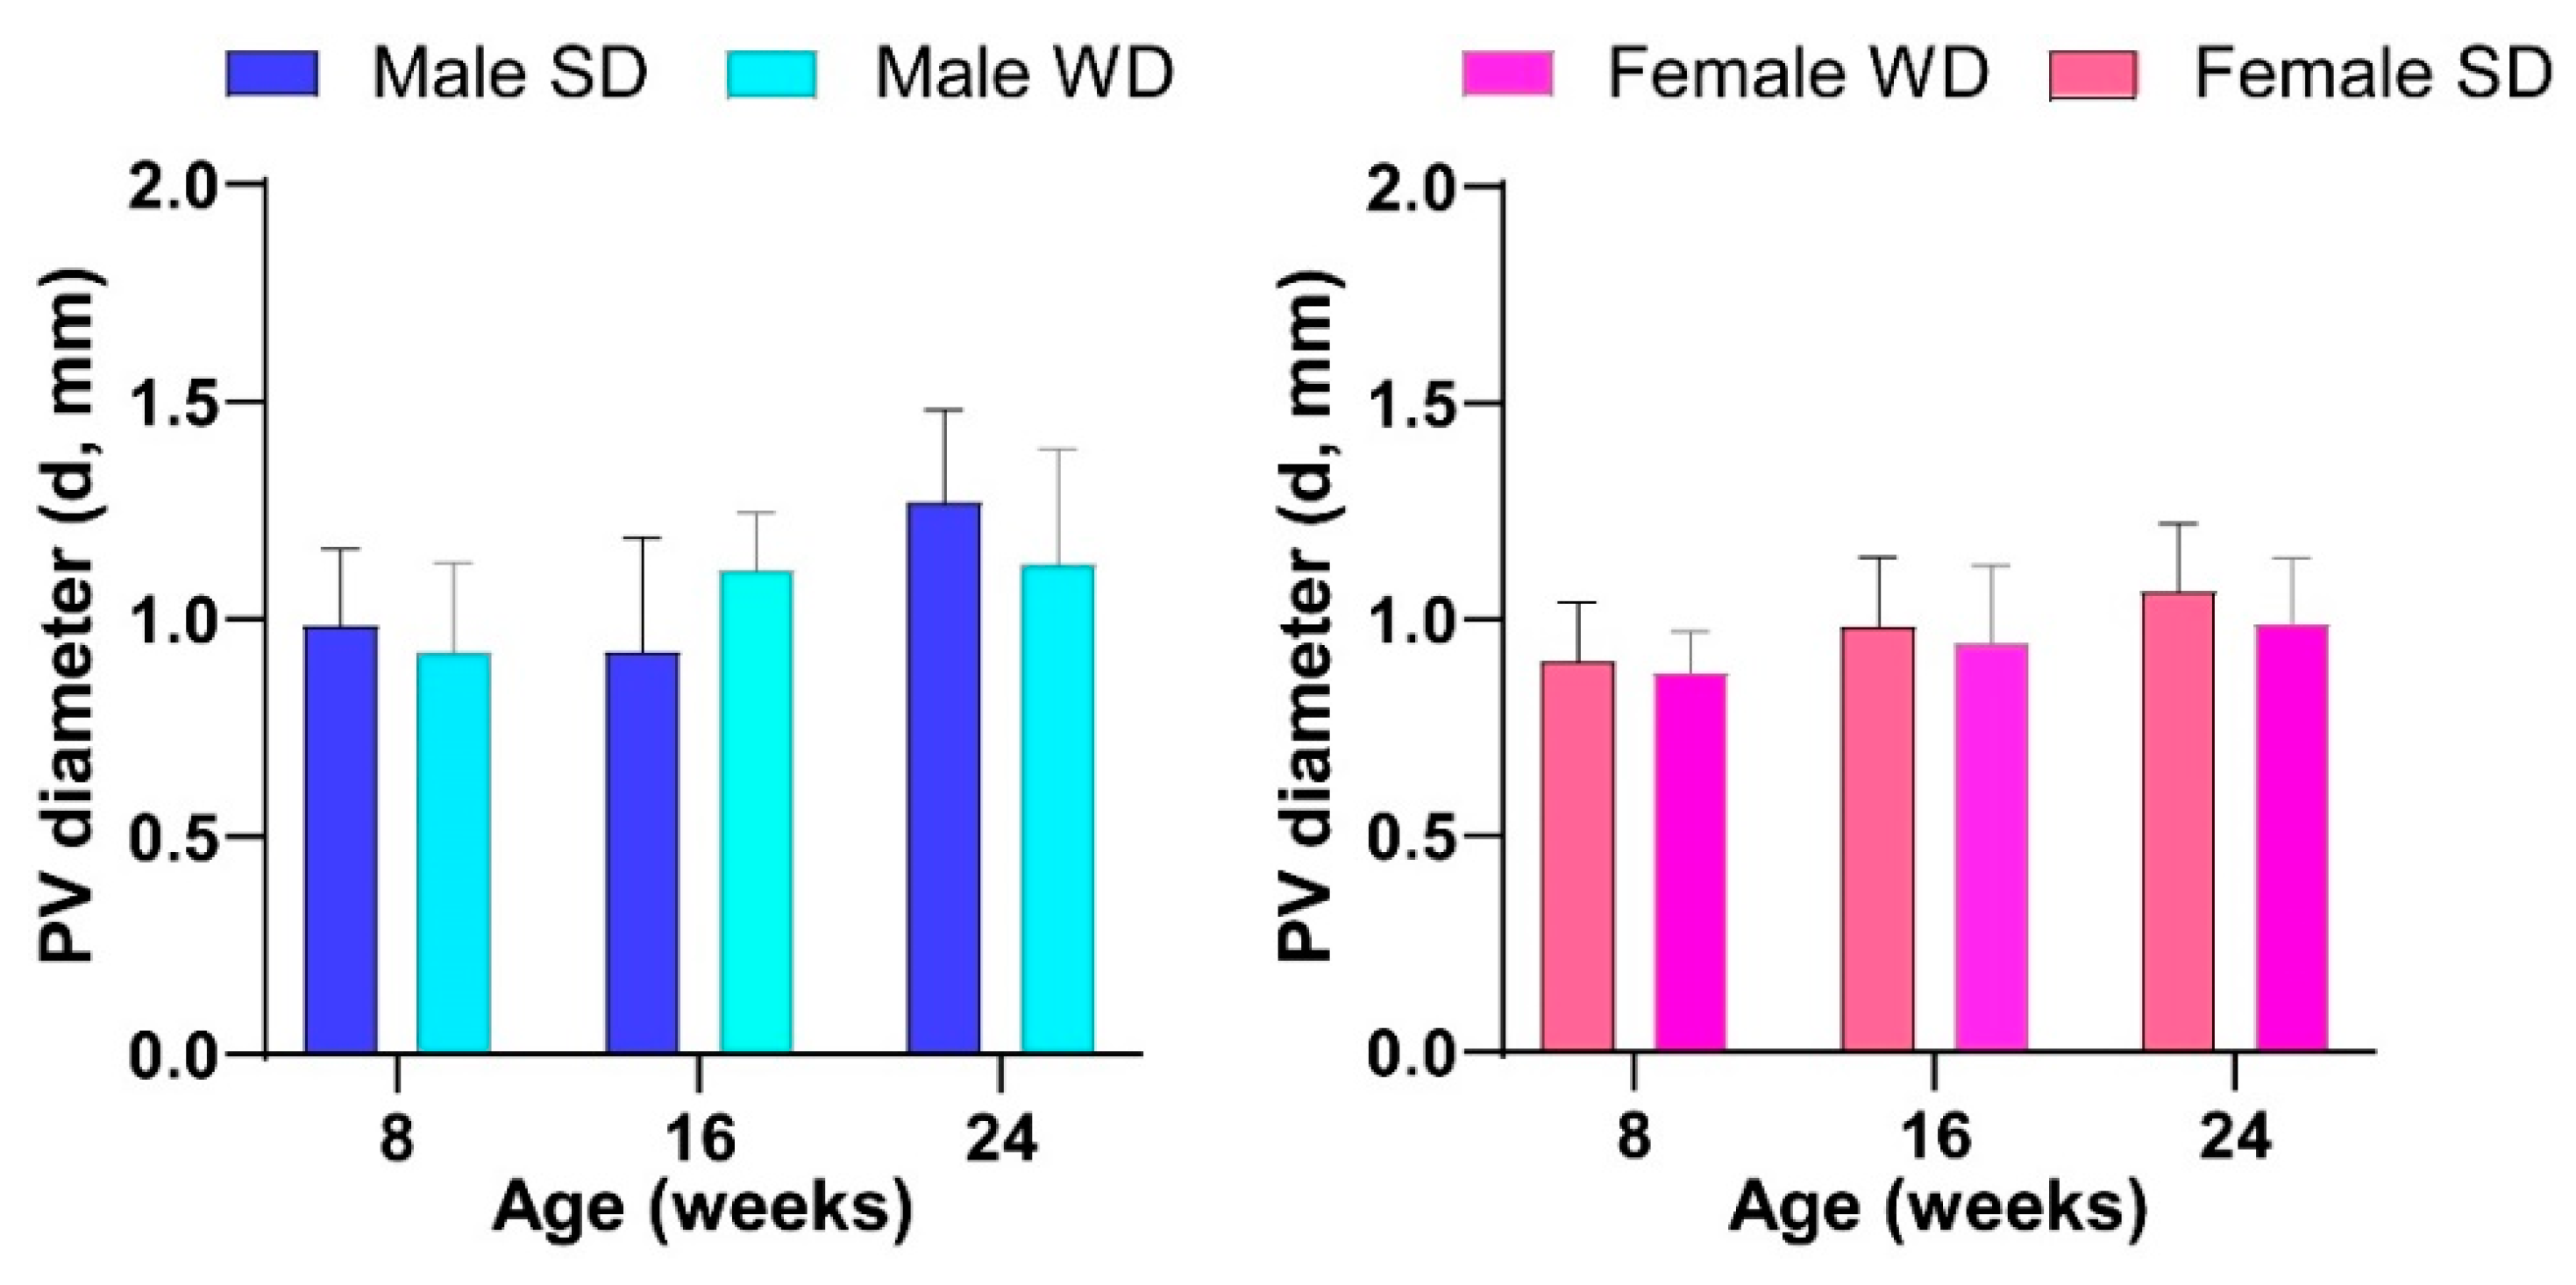

3.6. WD Causes Progressive Structural and Functional Changes in the Heart, Liver, and Kidney of C57Bl/6J Mice That Can Be Detected Early and Monitored In Vivo by HFUS